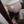

NT之前也是各种担心,担心要N次才能拍到,结果躺下,就听见医生咔咔咔的拍照,5分钟后就出结果了,通过好妈妈软件,平常已经看过N多个宝妈的单子,所以结果一出来我就知道一切正常,感谢平台各位宝妈的分享😘